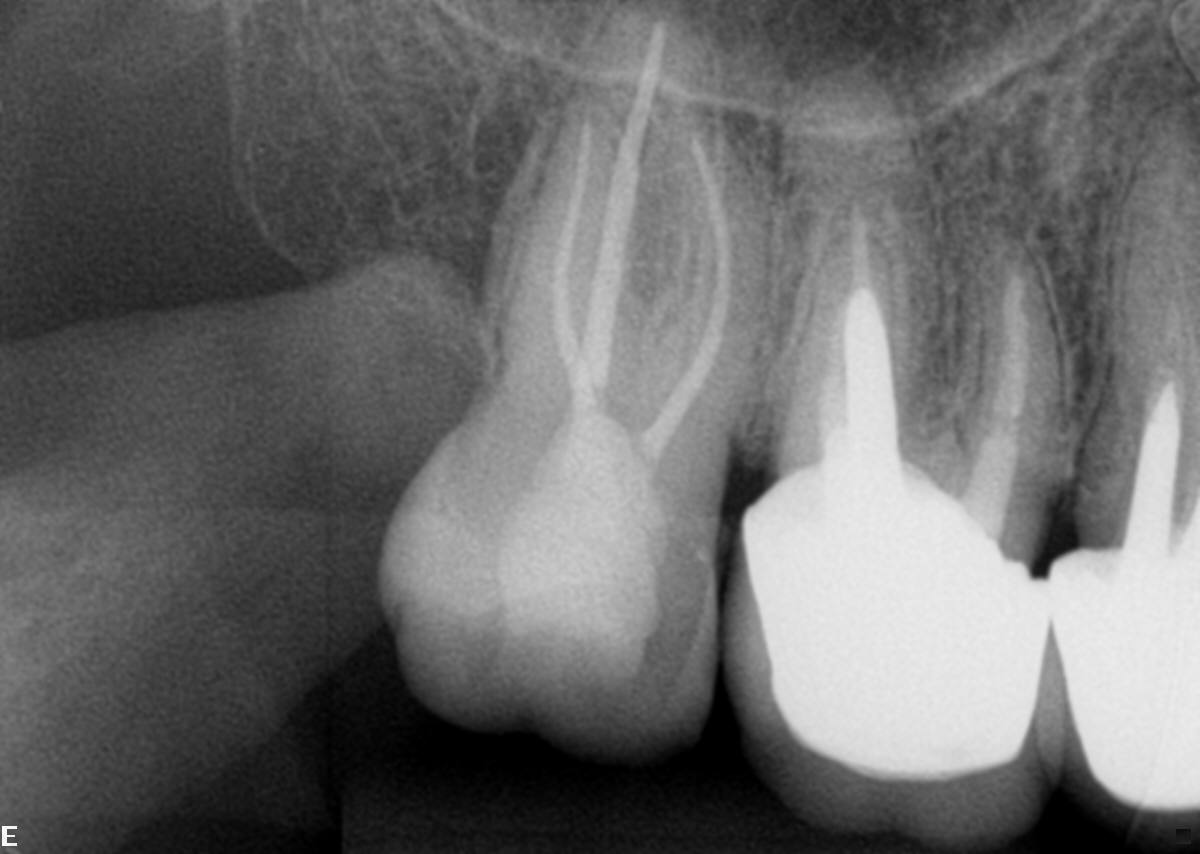

- Em seguida, relatou ter passado por um profissional que solicitou a ajuda de microscópio por não conseguir descer nos canais. Então, fizemos uma radiografia periapical onde constatou-se atresia em raiz distal, e atresia e curvatura em raiz mesial (Figura 3).

- A obturação deu-se na técnica de onda contínua de condensação usando o cimento AHPLUS da Dentsply (Figuras 5, 6 e 7).

Figura 2 Figura 3 Figura 4 Figura 5 Figura 6 Figura 7